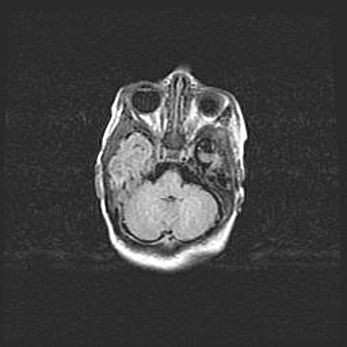

Церебральная ишемия II.

Возраст: 5 дней

Вес: 3400 г

Пол: женский

Окружность головы: 35 см

Срок гестации: 39 недель

Церебральная ишемия – это заболевание, характеризующееся недостаточностью (гипоксией) либо полным прекращением (аноксией) снабжения мозга кислородом по причине закупорки одного или нескольких сосудов. Это приводит к  что метаболическим расстройствам различной степени тяжести в тканях головного мозга, развитию коагуляционных некрозов и гибели нейронов.